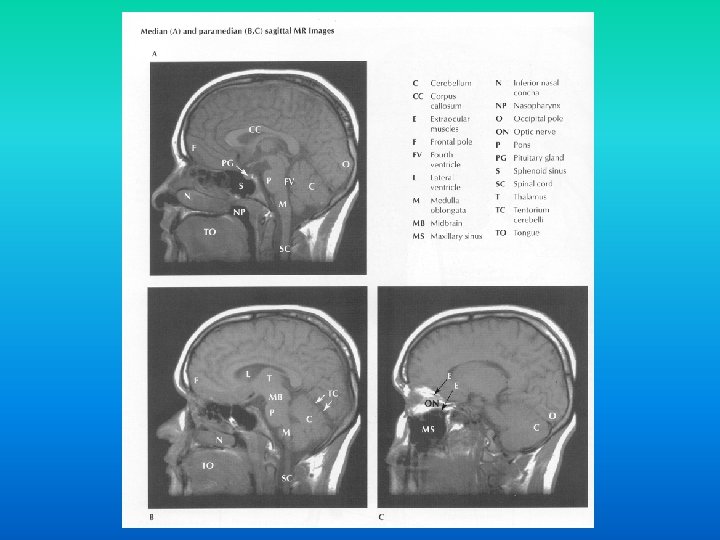

Diagnosticul imagistic al patologiei hipofizare Tehnici de explorare

Diagnosticul imagistic al patologiei hipofizare

Tehnici de explorare radioimagistica n in functie de bazele fizice sunt: n tehnici ce utilizeaza razele X: n n radiografii, mielografii, CT tehnici imagistice ce utilizeaza alte modalitati de obiectivare a structurilor anatomice: n ecografia, IRM